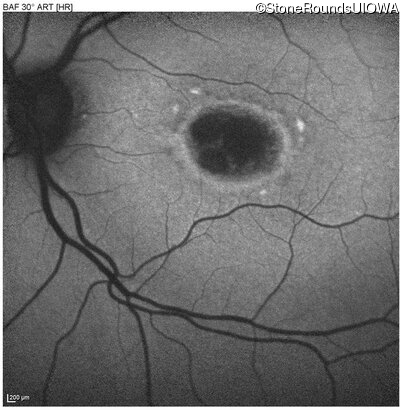

AR Stargardt Disease (IIA)

Age at visit:

47 years

OD

OS

20/125 -1

20/125 -2

Diagnosis & molecular findings

Disease

Gene

Allele 1 variant(s)

Allele 2 variant(s)

Inheritance mode

AR Stargardt Disease

ABCA4

Gly1961Glu GGA>GAA

Cys2150Tyr TGT>TAT

AR